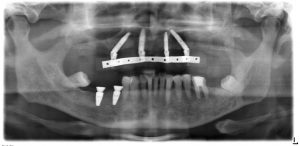

インプラントと仮歯が入った後のレントゲンです。

右下の欠損部には、2本のBLT4.1ΦRC10mmを2本埋入しています。